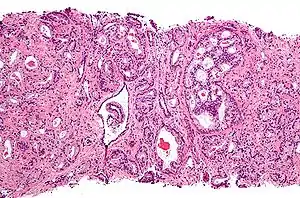

مقياس (نقاط) جليسون

يتم فحص عيّنات الأنسجة المأخوذة عن طريقة الخزعة بالمجهر للبحث عن الخلايا السرطانية وتقييم خواصّها المجهرية، التي يطلق عليها مقياس (نقاط) جليسون. مولد المضاد الغشائي للبروستات (PSA) هو عبارة عن إنزيم يُسمَّى الكاربوكسي بيبتيداز (بالإنجليزية: Carboxypeptidase) مسؤول عن تنشيط إنزيم فوليت هيدرولاز (بالإنجليزية: (Folate hydrolase). ويتمثل هذا البروتين في الأنسجة السرطانية في البروستات، وبالتالي يرتفع معدل نقاط جليسون.[36]

بعد إجراء خزعة البروستات، يفحص اختصاصي علم الأمراض العينات المأخوذة تحت المجهر، فإذا ما لوحظ وجود ورم سرطاني يُقرّر المختص درجة الورم. وهذه الدرجة تُبيّن مدى اختلاف أنسجة الورم عن أنسجة البروستات الطبيعية، وتضع تصوُّراً لسرعة نموّه. ويستخدم نظام جليسون لتقييم درجات أورام البروستات على مقياسٍ من 2 إلى 10، حيث الدرجة 10 في هذا النظام تشير إلى الحالة الأكثر اختلالاً. ثم يُعيّن اختصاصي علم الأمراض رقما من 1 إلى 5 للنمط الأكثر شيوعاً الذي لوحظ تحت المجهر، ويكرر ذلك على النمط الثاني الأكثر شيوعاً. ومجموع هذين الرَّقمين هو درجة غليسون. وهنالك طريقة أخرى تستخدم في بعض الأحيان تسمى نظام إيتمور-جيويت (بالإنجليزية: Whitmore-Jewett stage).